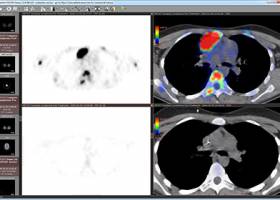

The protocol is applied to capture, exchange, and archive image data in picture archiving and communication systems (PACS). Nowadays, DICOM has been established as the leading standard for image data management in medical applications. Our evaluation shows that advanced visualization and suitable interfaces can also be found in the open source field and not only in commercial products.ĭigital imaging and communications in medicine (DICOM) has been released in 1993 by the American College of Radiology (ACR) and the National Electrical Manufacturers Association (NEMA). Weasis is superior for workflow optimization in clinical trials. Focusing on open source components, MIPAV is the best candidate for 3D imaging as well as DICOM communication. Interfaces needed for decentral viewing in web-based systems are offered by Oviyam, Weasis, and Xero. The viewers ImageJ, MicroView, MIPAV, and OsiriX Lite offer all included 3D-rendering features for advanced viewing. Suitable DICOM interfaces for central viewing in hospitals are provided by GingkoCADx, MIPAV, and OsiriX Lite. On the average, 4.48 and 1.43 of overall 8 2D and 5 3D image viewing criteria are satisfied, respectively. They include (i) platform, (ii) interface, (iii) support, (iv) two-dimensional (2D), and (v) three-dimensional (3D) viewing. The evaluation criteria are obtained from application scenarios in clinical research rather than patient care.

Imaging biomarkers and image-based surrogate endpoints in clinical trials and medical registries require DICOM viewer software with advanced functionality for visualization and interfaces for integration. The digital imaging and communications in medicine (DICOM) protocol is the leading standard for image data management in healthcare.